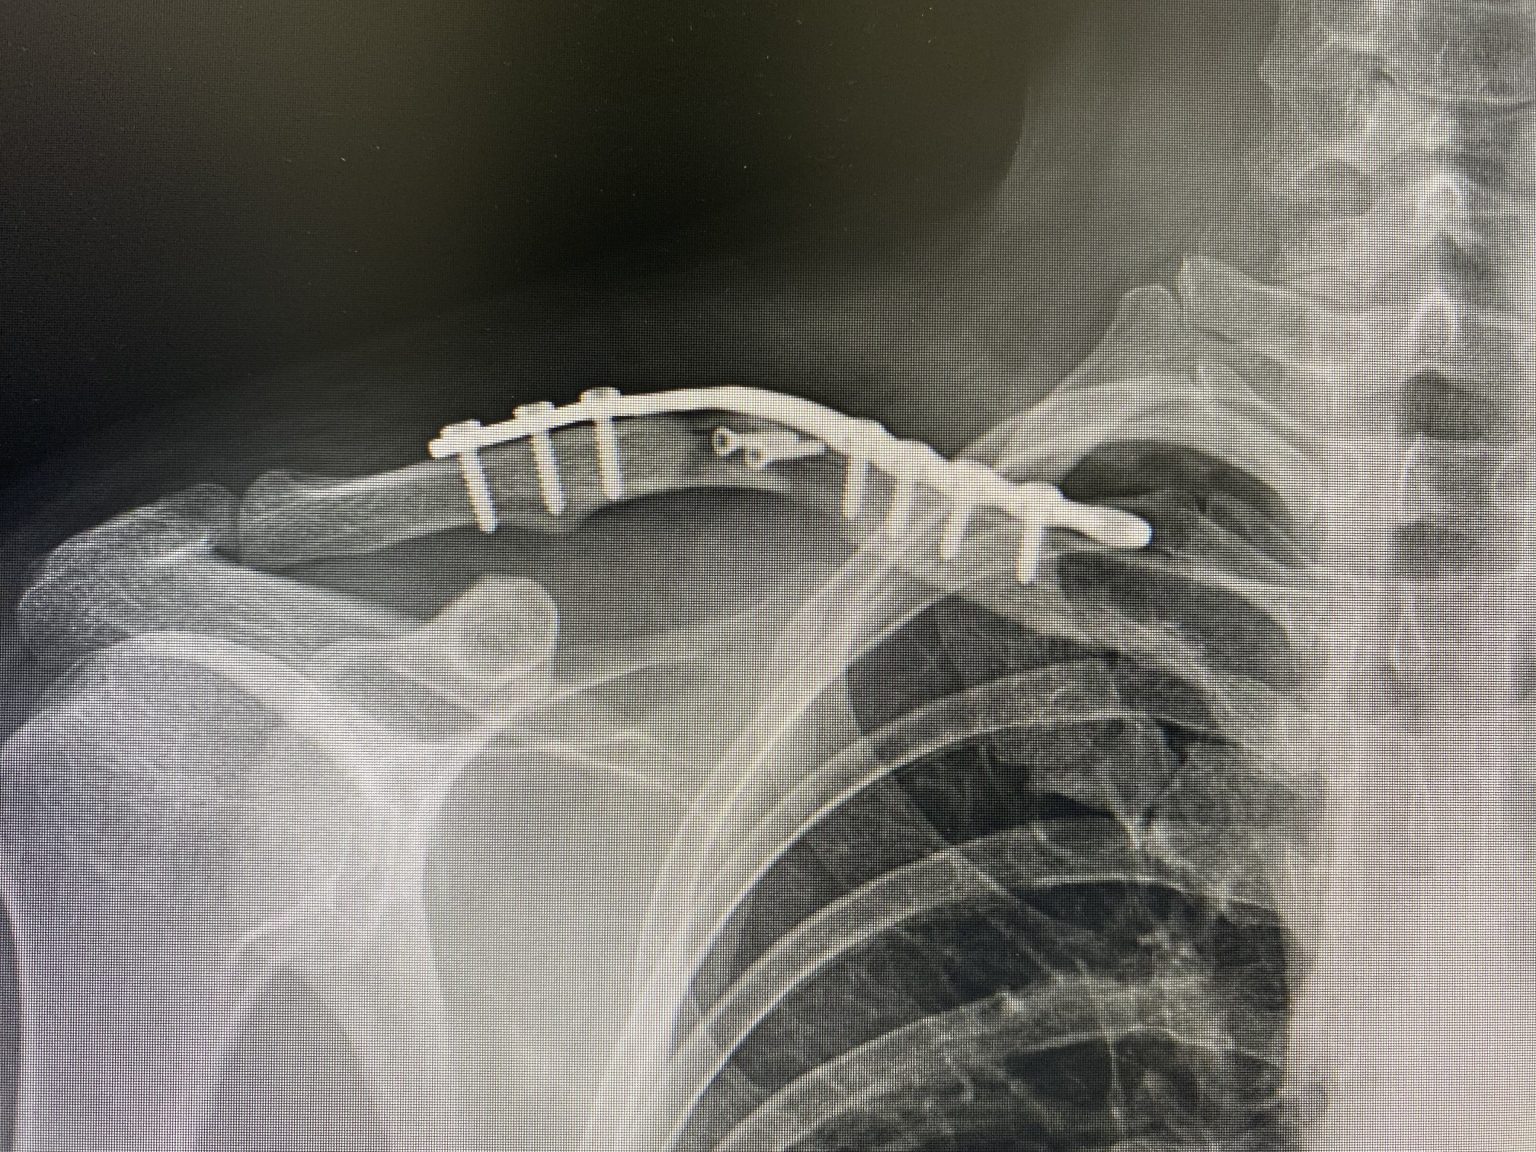

Broken clavicle, before and after my surgery r/XRayPorn How To Shower After Clavicle Surgery Recovery involves exercises and sling use for immobilization. Protect the fractured clavicle 2. rehabilitation after clavicle fracture phase one: • you may shower with the dressing in place. Cleanse around the area or. you may shower after 3 days. Do not submerge the wounds in water (bathtub, pool, lake) for at least 2 weeks. this video. How To Shower After Clavicle Surgery.